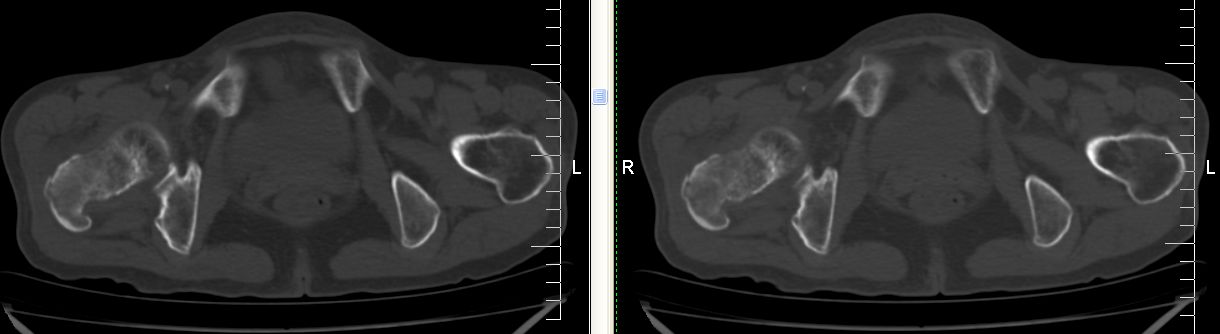

以下是引用余辉在2007-12-5 17:25:00的发言:[br]右侧股骨颈及粗隆区略显膨胀,密度增高略呈不均匀毛玻璃样改变,骨皮质毛糙,考虑1骨纤2骨髓瘤3转移瘤,建议上传软组织窗